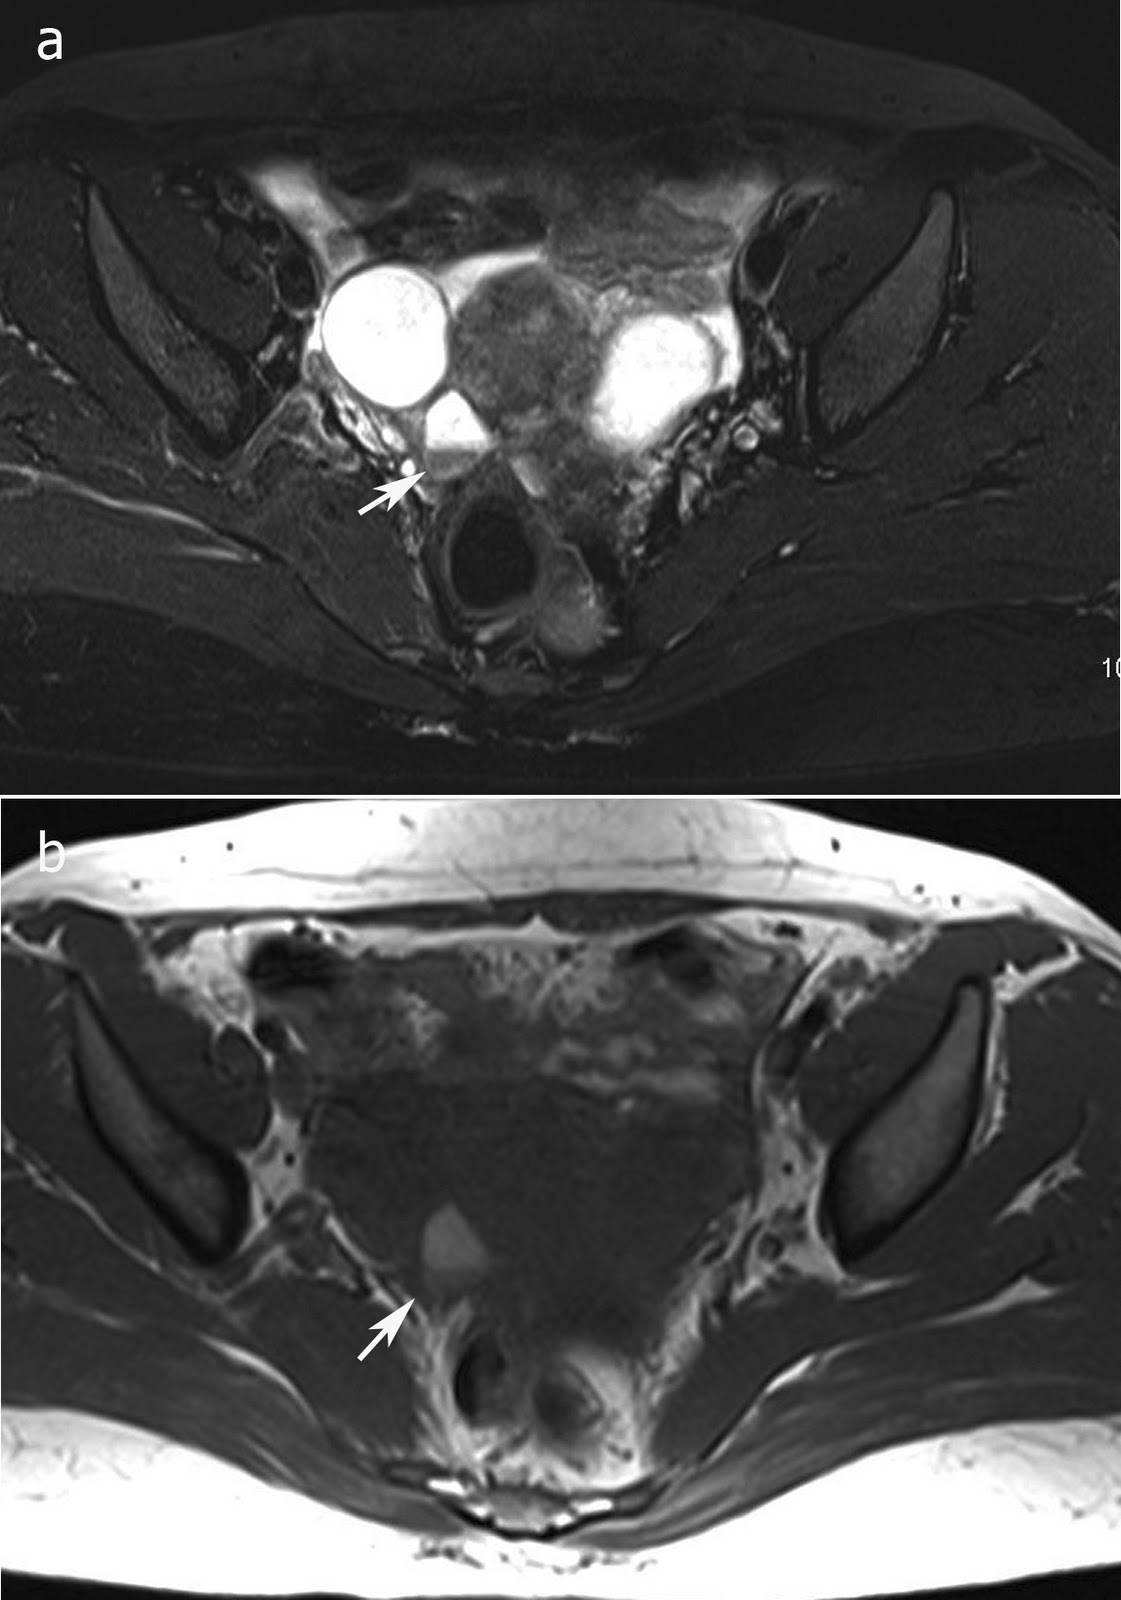

Endometrioma Ovárico Y Dolor Lumbar, Disfunciones ginecológicas y dolor de espalda lumbar y ciático - Causas y tratamiento, 9.8 MB, 07:08, 25,949, FisioOnline, 2012-04-16T10:54:20.000000Z, 3, Ovarian endometriosis. Intraoperative photograph (a) showing an, www.researchgate.net, 850 x 665, jpeg, WebEl endometrioma ovárico o ‘quiste de chocolate’ es el término aplicado para describir un quiste ovárico recubierto con tejido endometrial, histológica y funcionalmente. WebEl endometrioma es un quiste benigno en el ovario que puede causar síntomas como cólicos abdominales intensos, dolor durante el contacto íntimo,. WebHabitualmente el endometrioma es un hallazgo ecotomográfico en pacientes que consultan por infertilidad. Es frecuente que esté asociado a otros quistes en el mismo., 20, endometrioma-ovarico-y-dolor-lumbar, Novedades y Muebles WebEl endometrioma ovárico o ‘quiste de chocolate’ es el término aplicado para describir un quiste ovárico recubierto con tejido endometrial, histológica y funcionalmente. WebEl endometrioma es un quiste benigno en el ovario que puede causar síntomas como cólicos abdominales intensos, dolor durante el contacto íntimo,. WebHabitualmente el endometrioma es un hallazgo ecotomográfico en pacientes que consultan por infertilidad. Es frecuente que esté asociado a otros quistes en el mismo.

WebLos síntomas dependen de la ubicación de los implantes. La tríada clásica de síntomas incluye dismenorrea, dispareunia e infertilidad, pero los síntomas también pueden incluir. WebUn dolor de espalda en la zona lumbar puede deberse a la disfunción del útero y ovarios. Aquí te enseñaremos cómo detectar si ese dolor se debe. WebLa endometriosis, definida como la presencia de tejido endometrial –glandular y estromal– fuera de la cavidad uterina, es una enfermedad relativamente frecuente en mujeres. WebEl endometrioma ovárico es frecuente, muy a menudo asociado a otras lesiones endometriósicas de la pelvis. La clínica está dominada por el dolor crónico. WebLa endometriosis es un síndrome bastante doloroso en el cual el tejido que reviste el útero, conocido como endometrio, crece en otras regiones del abdomen como en los ovarios,. WebLa endometriosis es una enfermedad caracterizada por la aparición de trozos de tejido de la capa interna del útero, llamada endometrio, fuera del útero. La. WebDesde 5-10% hasta el 50% de las pacientes con infertilidad o dolor pélvico crónico, 1 de cada 10 mujeres en el mundo durante su vida reproductiva (15-49 años) padecen. WebUn dolor consuetudinario en la parte baja de la espalda puede ser indicio de cáncer de ovario. El cáncer de ovario es el sexto más consuetudinario a caballo entre las mujeres,.

WebEl endometrioma es un quiste ovárico originado por tejido endometrial, el contenido está constituido por un líquido espeso de aspecto denso y de color café muy. WebEndometrosis y adenomiosis, otra causa de dolor abdominal y lumbar. Salud Hormonal ¿Algunas de vosotras tenéis, dolor justo antes de la regla, o durante ella,. WebLos signos clínicos del endometrioma ovárico no son muy diferentes de los de otras localizaciones de la enfermedad. Se observa dismenorrea, dispareunia.